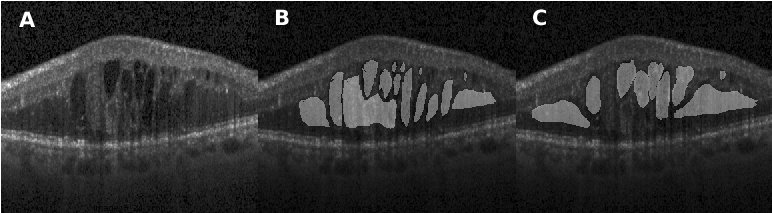

Figure 4.5 depicts the comparison of our method with the one reported in Chiu et al. [19] for three segmentation attempts carried out complex retinopathy conditions. It is found that Chiu’s method performs a slight over-segmentation near the bottom area. The segmentation results carried out with our method are closer to those which have been manually segmented. In Fig. 4.6, three images are shown which depict segmentation results on concrete and non-obvious fluid edema. The over-segmentation noted earlier can also be observed , as well as a false segmentation happening in the region on the left-hand side. Again, the results obtained with our method have a better agreement with those obtained via manual segmentation. Furthermore, our results are more adherent to target based on image content. This is also found in Fig. 4.7 where additional results are presented from the segmentation of an example of fluid edema. Quantitatively, we compared the Dice overlap coefficient and -value of Wilcoxon matched-pairs test for the DME region. Dice coefficients were calculated for all 10 patients and the process was repeated as per[19]. Specifically, the Dice coefficient was calculated based on all test images and the Wilcoxon matched-pairs test was calculated based on the mean Dice coefficient across all patients for our automated method and for the corresponding results from two graders. It was found that the Dice coefficient of our approach is standing for mean and standard deviation which outperforms reported in [19] (the higher, the better). Both methods are comparable with the Dice coefficient between manual graders ( ). The -value for our approach is , which is also better than reported in Chiu et al. [19] (where a coefficient value of indicates perfect agreement).